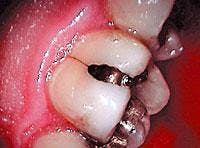

Even with corrected vision, you will not get the precise level of decay removal necessary without using quality magnification and a caries detector. Unless you are 28 and really on it, you are blowing it if you are doing posterior composites without enhanced sensory advantages.

The reality is the rest of us need microscopes. For routine work by the salt of the profession, good lighting, corrected magnification, and a caries detector are musts.